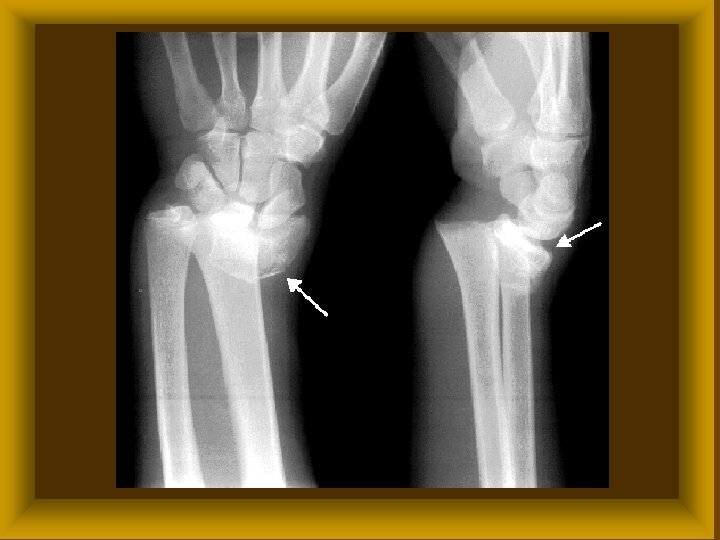

Subluxatio

FICAM ( LUXATIO ) Ø Luxatio completa ( teljes ) Ø Subluxatio ( részleges ) Ø Veleszületett (csípőficam) Ø Szerzett * traumás * habituális * recidiv

FICAM ( LUXATIO ) TÜNETEI Ø Szubjektív fájdalom * működési zavar Ø Objektív * alakváltozás * rugalmas rögzítettség *

FICAM ( LUXATIO ) KEZELÉSE Ø Repositio ( narkózisban ) * konzervativ * műtéti Ø Rögzítés Ø Rehabilitatio